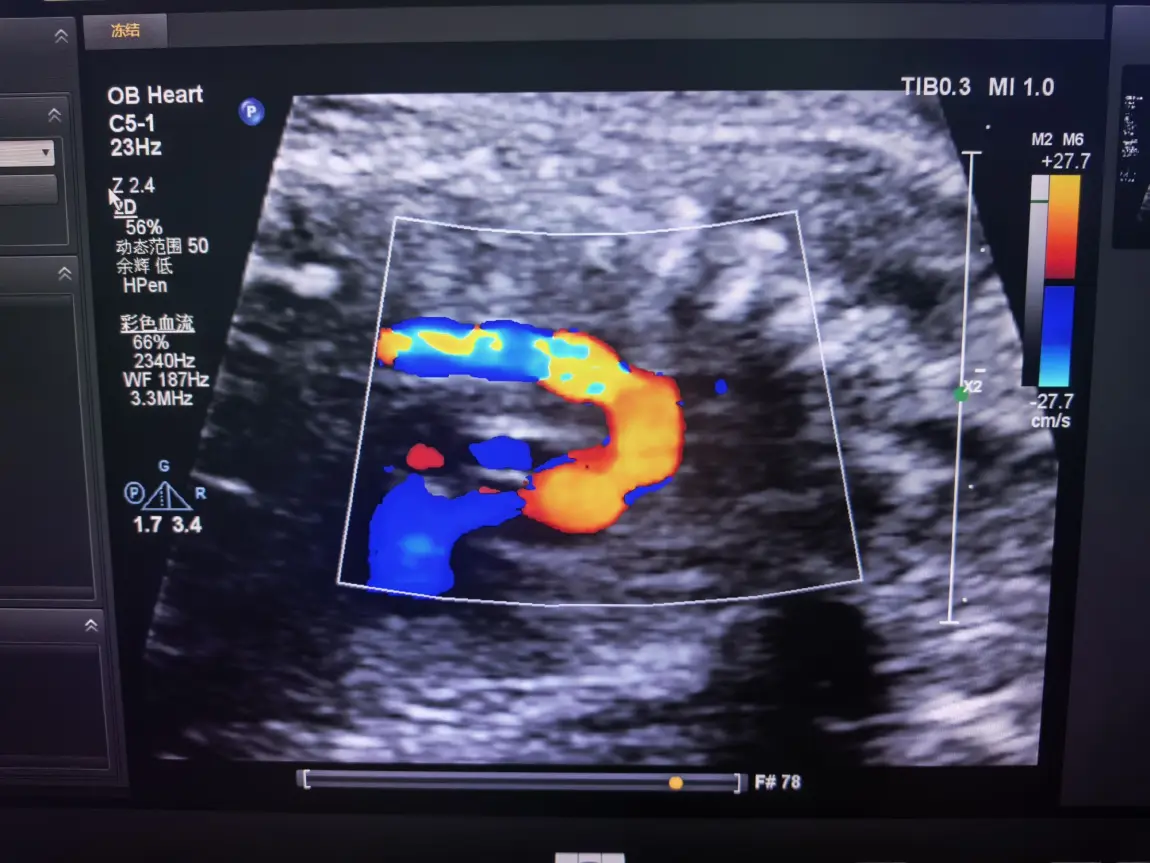

作为超声科医生,诊室里的超声屏从清晨亮到下午,屏幕上脏器的轮廓、血流的走向,容不得半点马虎,每一次探头移动都要精准对准毫米级的细节。一整天下来,神经始终绷得紧紧的,直到脱下白大褂,指尖触到小鹏P7+温润的车门把手,那份职业带来的沉重才慢慢卸下。遇上值夜班,忙到深夜走出医院,浑身疲惫得连开车的力气都没有,我便躺在副驾座椅,裹着车内的静谧睡上一小会儿,这短暂的休憩,足以驱散通宵的倦意。